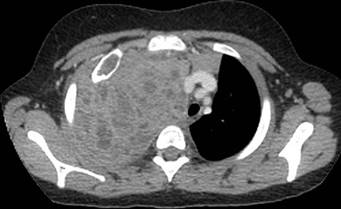

Dada la clínica se decide realizar radiografía de tórax (Figura 1) en la que se identifica derrame pleural derecho y una masa en segmento anterior del lóbulo superior derecho (LSD) con una lesión lítica expansiva en el segundo arco costal anterior derecho. Se amplia estudio con ecografía en la que se visualiza una masa pleural / pulmonar en segmento anterior de LSD con probable afectación mediastínica, derrame pleural derecho y alteración en la cortical del segundo arco costal anterior derecho. Se decide realizar TC torácico con contraste (Figura 2), (Figura 3) y (Figura 4) para valorar extensión y características de la lesión, identificándose una masa de aproximadamente 120x130x100 mm que ocupa casi todo el hemitórax derecho, heterogénea, con múltiples áreas quístico-necróticas en su interior. Condiciona desviación contralateral del mediastino y su infiltración, comprimiendo la vena cava inferior, sin claro plano de separación y contactando con el pericardio con signos de infiltración de la aurícula derecha. Comprime el bronquio principal derecho y sus ramas, condicionando atelectasia parcial secundaria y contacta con el segmento extrapericárdico de la arteria pulmonar derecha y ambas venas pulmonares derechas.

Figura 4: Se objetiva infiltración de la pared costal sin poder determinar claramente si el origen de la masa es pulmonar o extrapulmonar. Lesión lítica expansiva en segundo arco costal derecho.

Se objetiva infiltración de la pared costal y lesión lítica expansiva en segundo arco costal derecho. Parénquima pulmonar con un nódulo milimétrico en LSD.